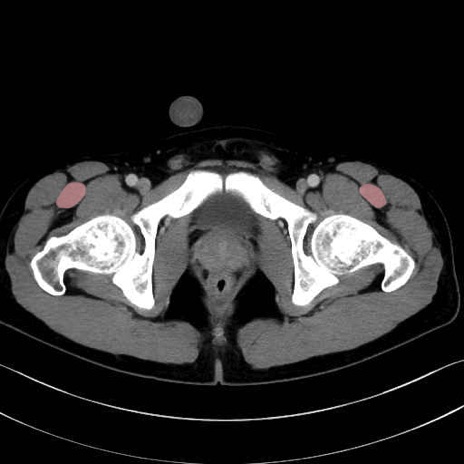

大腿筋膜張筋 (Tensor fasciae latae)

大腿直筋 (Rectus femoris)